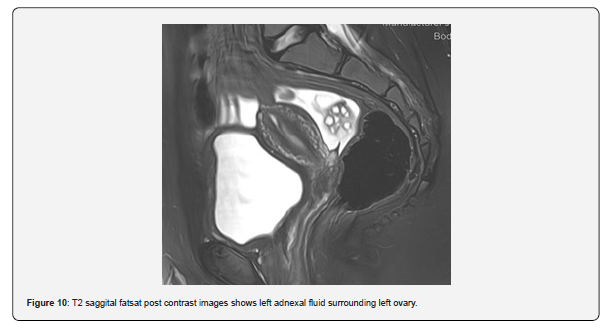

The patient is a 12-year-old girl who presented to emergency department with severe left-sided abdominal pain associated with persistent vomiting for the past two days. On physical examination left flank tenderness was noted with radiation to suprapubic area, there was no diarrhea or fever. Pelvic ultrasound with Doppler demonstrated bilaterally enlarged ovaries with small follicles with a markedly enlarged left ovary showing reduced vascularity and no evidence of identifiable ovarian cyst (Figures 1-4). Magnetic resonance imaging (MRI) demonstrated bilateral ovarian enlargement with multiple small follicles, assuming polycystic ovarian morphology. The left ovary was significantly enlarged, positioned posterior to the uterus and showed stromal edema with decreased post-contrast enhancement compared to contralateral side, findings consistent with ovarian torsion (Figures 5-10).

No definite ovarian cyst was identified on MRI. Mild free fluid was noted in the left adnexa. Patient underwent emergency laparoscopy and ovarian torsion was confirmed intraoperatively. Left ovary was found enlarged and torsed with two twists. A small ovarian cyst measuring approximately 2x2 cm was detected. Ovarian sparing laparoscopic detorsion of the left ovary was performed with cyst marsupialization. Patients were discharged on postoperative day 3 in stable condition. Follow-up visit in clinic after one week showed uneventful recovery. This case report highlights the importance of prompt diagnosis of ovarian torsion for timely surgical intervention even in absence of detectable cyst on imaging. aiming to preserve ovarian torsion and future fertility.